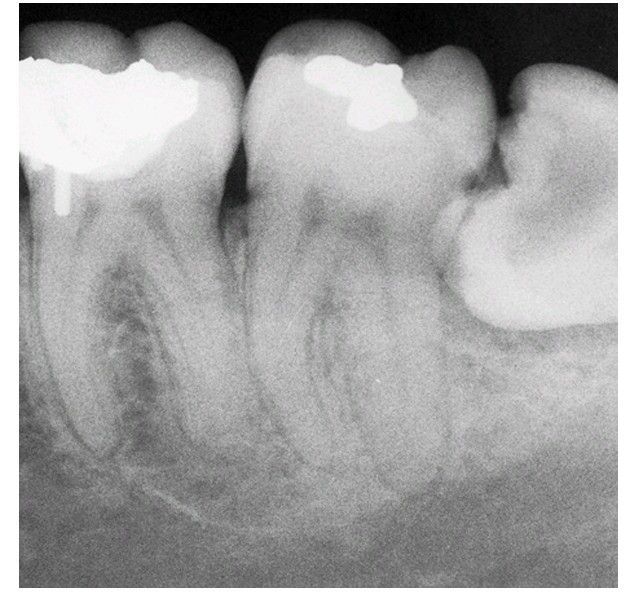

Impacted 3rd molar

Radiograph of caries in a mandibular impacted molar.